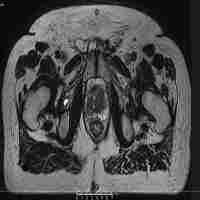

| Abstract | In this study, we assess the dosimetric qualities and usability of planning for 1.5 T MR-Linac based intensity modulated radiotherapy (MRL-IMRT) for various clinical sites in comparison with IMRT plans using a conventional linac. In total of 30 patients with disease sites in the brain, esophagus, lung, rectum and vertebra were re-planned retrospectively for simulated MRL-IMRT using the Elekta Unity dedicated treatment planning system (TPS) Monaco (v5.40.01). Currently, the step-and-shoot (ss) is the only delivery technique for IMRT available on Unity. All patients were treated on an Elekta Versa HDTM with IMRT using the dynamic multileaf collimator (dMLC) technique, and the plans were designed using Monaco v5.11. For comparison, the same dMLC-IMRT plan was recalculated with the same machine and TPS but only changing the technique to step-and-shoot. The dosimetric qualities of the MRL-IMRT plans, to be evaluated by the Dose Volume Histograms (DVH) metrics, Homogeneity Index and Conformality Index, were compared with the clinical plans. The planning usability was measured by the optimization time and the number of Monitor Units (MUs). Comparing MRL-IMRT with conventional linac based plans, all created plans were clinically equivalent to current clinical practice. However, MRL-IMRT plans had higher dose to skin and larger low dose region of normal tissues. Furthermore, MRL-IMRT plans had significantly reduced optimization time by comparing conventional linac based plans. The number of MUs of MRL-IMRT was increased by 23% compared with ss-IMRT, and no difference from dMLC-IMRT. In conclusion, clinically acceptable plans can be achieved with 1.5 T MR-Linac system for multiple tumor sites. Given the differences in machine characteristics, some minor differences in plan quality were found between MR-Linac plans and current clinical practice and this should be considered in clinical practice. |